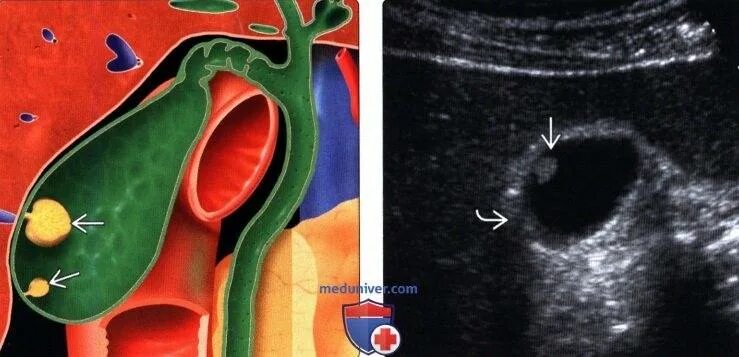

Как избавиться от полипов в желчном пузыре